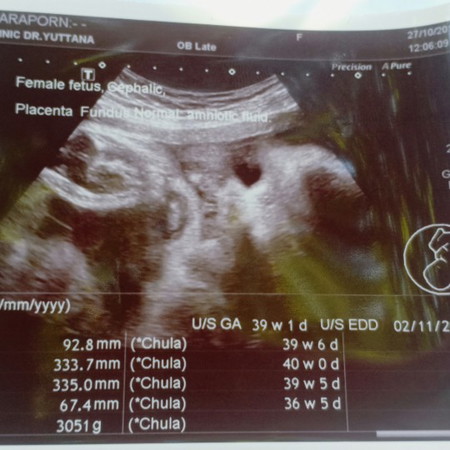

กำหนด11/11/62 ทำไมไม่ตงกับซาว

น้ำหนักแม่ขึ้นมา13โล หมอสั่งคุมน้ำหนักแล้ว กัวจะคลอดน้องเองไม่ได้